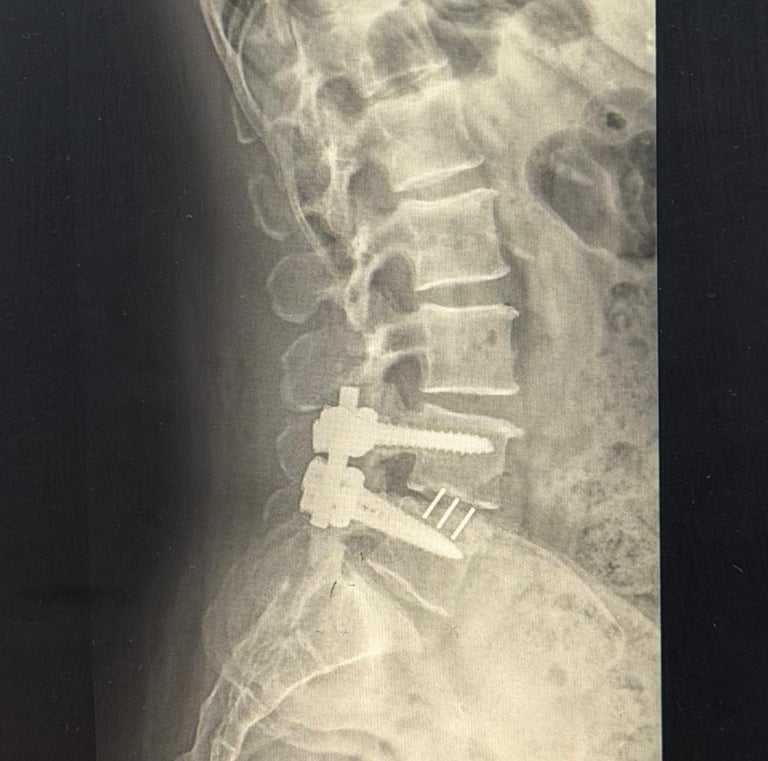

En Let´s Rehab, cada sesión está diseñada en torno a ti, adaptándonos a tus necesidades tras una cirugía o lesión.

Momentos reales de recuperación y cuidado personalizado.